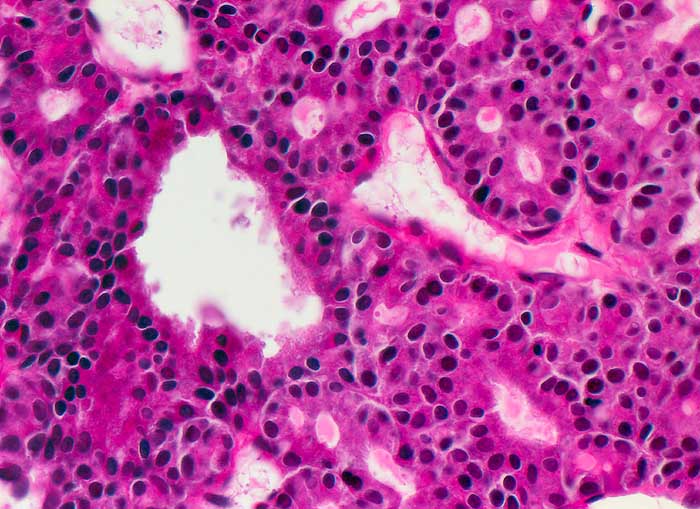

La nésidioblastose du pancréas, terme de racine grecque signifiant tumeur des ilots (de Langerhans), est, avec l'hyperplasie adénomateuse focale, la forme la plus fréquente de l'hyperinsulinisme familial.